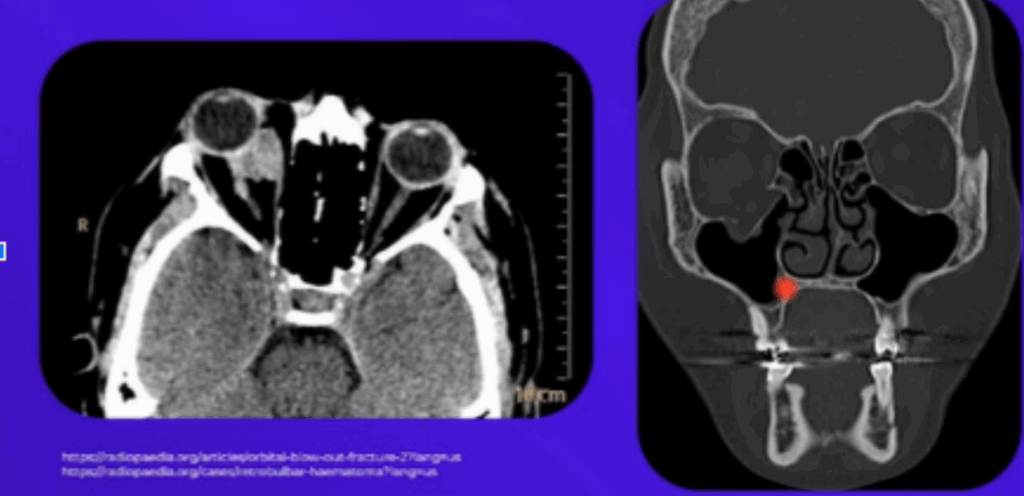

O exame padrão-ouro para o diagnóstico é a Tomografia Computadorizada (TC) de face com reconstrução 3D, que oferece uma visualização detalhada das estruturas ósseas nos planos axial, coronal e sagital.

- Hematoma retrobulbar: Acúmulo de sangue atrás do globo ocular que pode levar à perda de visão definitiva.

- Fratura Orbital: A órbita é composta por 7 ossos, sendo as paredes medial e inferior as mais frágeis. A fratura do tipo “Blow-Out” ocorre por um aumento súbito da pressão intraorbital, que leva à fratura dessas paredes frágeis e herniação do conteúdo orbitário para os seios maxilar e etmoidal. Os sinais clássicos incluem diplopia, enoftalmia (afundamento do globo ocular) e restrição da motilidade ocular, especialmente na elevação do olhar, devido ao encarceramento do músculo reto inferior.